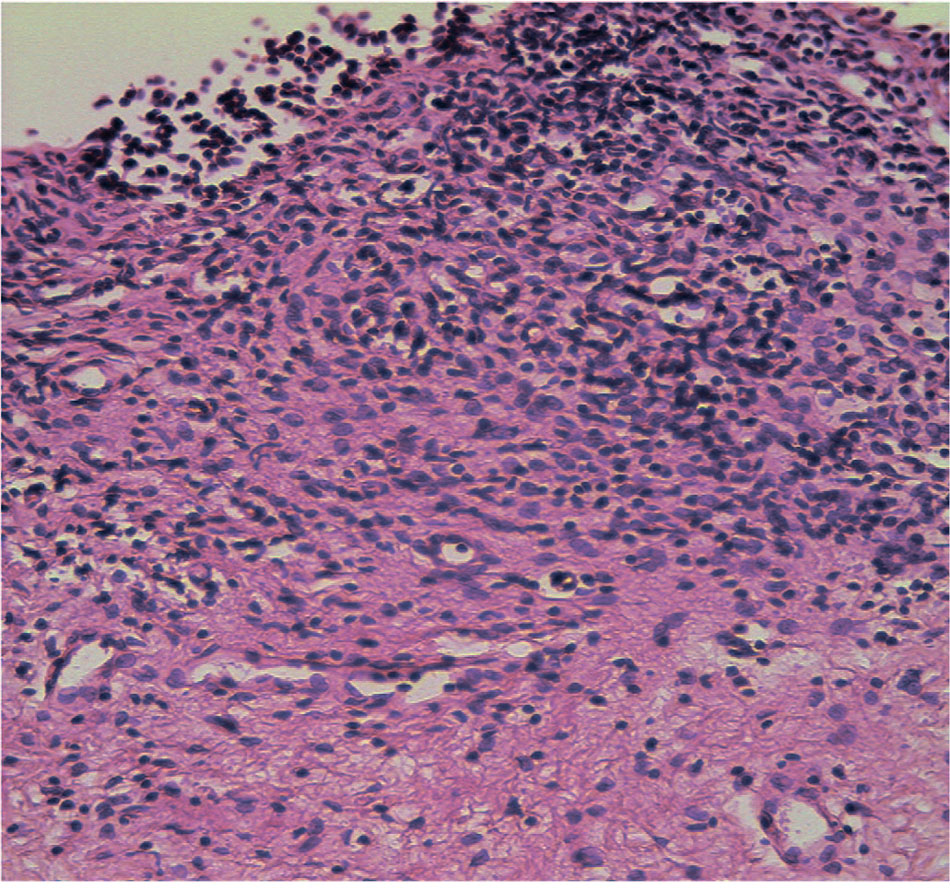

Рис. 1. Фиброз собственной пластинки в виде рубцовой трансформации. Выраженная очаговая инфильтрация лимфоцитами. Окраска гематоксилином и эозином, х 246,4

Fig. 1. Fibrosis of the lamina propria in the form of scar transformation. Pronounced focal infiltration by lymphocytes. H&E, x 246,4

Морфологический анализ полученных в ходе видеоцистоскопии биоптатов стенки мочевого пузыря подтвердил наличие хронического воспаления у всех 58 пациенток (100%), о чем свидетельствует выявленная лимфоцитарная инфильтрация (рис.1, 2). Длительный воспалительный процесс в стенке мочевого пузыря сопровождался склерозированием в 70,1% случаев (у 41 женщины) (рис.1, 3). Результаты гистопатологического исследования показали нарушение целостности уротелия в 86,2% случаев (у 50 пациенток, соответственно), причем в 63,8% отмечалось уплощение уротелия вплоть до одного слоя, отсутствие слоев и/или связи между эпителиоцитами до полной денудации (рис. 2).